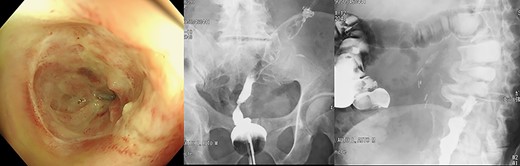

A 70-year-old man diagnosed with lower rectal cancer was admitted to our hospital for treatment. Colonoscopy revealed an uncirculated ulcerated tumor at the lower rectum. Tubular adenocarcinoma was diagnosed by histologic examination of the endoscopic biopsy specimen. Abdominal computed tomography showed limited thickening of the wall of the rectum, but there was no swelling of regional lymph nodes. No apparent distant metastasis including liver or lung metastasis was detected. Laparoscopic ultra-LAR and colorectal anastomosis (CRA) with protective loop ileostomy were performed. The intraabdominal drain and transanal drain were removed, and diet intake started 4 days after surgery. Massive diarrhea caused a rapid decrease in blood pressure, and vital signs stabilized immediately after treatment with infusion and vasopressor 11 days after surgery. Vancomycin was orally administered for the treatment of Clostridium difficile infection. The cause of shock turned out to be an ischemic change of the oral side of the anastomosis by endoscopic examination. Repeated endoscopic balloon dilatation for the stenotic portion for 5 months failed, and stoma care was firmly refused by the patient during this period (Fig. 1). Two ways of surgery were proposed for further treatment as the next step. One was permanent end colostomy, and the other was DCAA. Permanent stoma was refused and the latter one was selected. The operative procedure was performed as described in the following.

Endoscopic findings and gastrograffin enema 5 months after initial surgery.